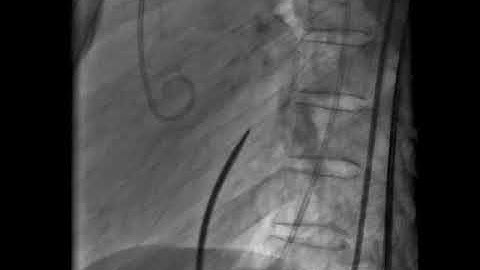

How to echocardiographically guide a trans-septal puncture - PITLOC Protocol